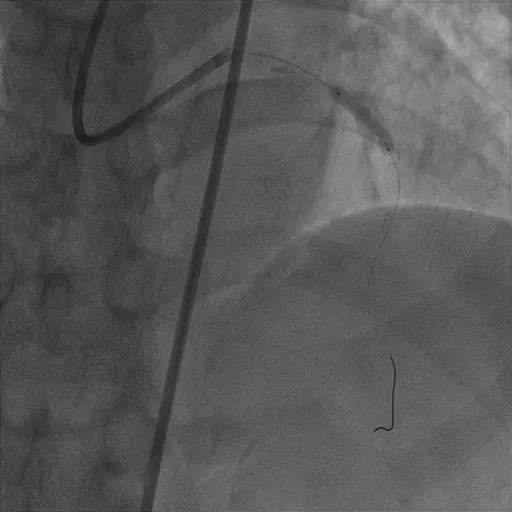

考虑到钙化结节仍较大,钙化环未充分打开,为彻底解决患者的血管病变,崔永亮医师再次穿刺股动脉,经8F指引导管送入2.25mm旋磨头,再次对前降支病变由14万转降速至10万转对病变反复打磨抛光。根据以往经验,透析患者极易反复发生支架内再狭窄的问题,结合IVUS复查结果,崔永亮医师决定采用4.0×30mm药物球囊进一步处理病变,以达到“介入无植入”的效果。术后IVUS显示钙化结节少量残留,管腔面积增大一倍有余上,达6.68mm²,堪称效果完美。

4.0×30mm药物涂层球囊植入

术后造影;术后IVUS管腔面积